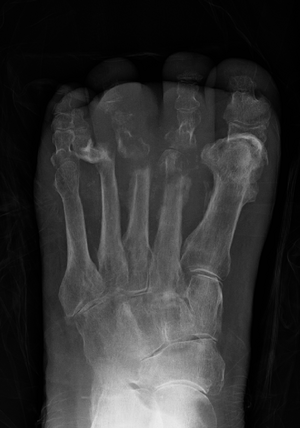

| Osteomyelitis of the 1st toe | |

Osteomyelitis (OM) is the infectious inflammation of bone marrow.[1] Symptoms may include pain in a specific bone with overlying redness, fever, and weakness.[1] The feet, spine, and hips are the most commonly involved bones in adults.[2]

Radiographs and CT are the initial method of diagnosis, but are not sensitive and only moderately specific for the diagnosis. They can show the cortical destruction of advanced osteomyelitis, but can miss nascent or indolent diagnoses.[23]

Diagnosis of osteomyelitis is often based on radiologic results showing a lytic center with a ring of sclerosis.[13] Culture of material taken from a bone biopsy is needed to identify the specific pathogen;[27] alternative sampling methods such as needle puncture or surface swabs are easier to perform, but cannot be trusted to produce reliable results.[28][29]